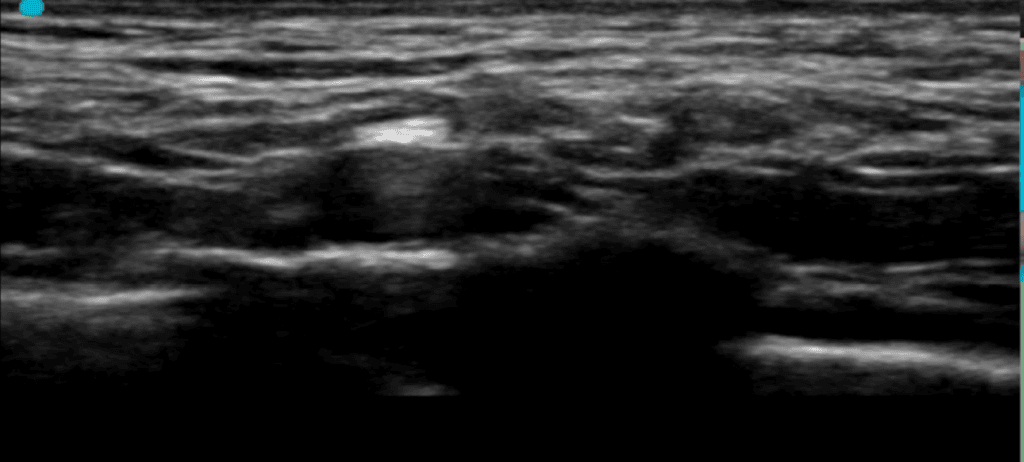

En la imagen ecográfica se muestra la arteria sobre la primera costilla, por debajo de la porción horizontal del músculo omohioideo.

La realización de este abordaje debe de tener en cuenta la distribución del plexo a lado y lado de la arteria, tal y como veremos en la imagen a continuación.

En esta secuencia de tres imágenes se representa la imagen ecográfica del plexo en la base del cuello, es decir, el abordaje supraclavicular.

- El transductor está colocado en paralelo al borde posterior de la clavícula, apuntando en sentido caudal

- Se observa el conjunto de arteria subclavia y plexo debajo de la porción horizontal del músculo omohioideo (OH en la imagen) y por encima de la primera costilla.

- El este paciente en particular, se observan en la cara superoexterna de la arteria, los troncos superior (TS) y medio ™ envueltos por la fascia del plexo, acompañados por el nervio supraescapular (SE). En este caso, el nervio SE está empezando a separarse del plexo.

- En la cara inferior se observan las raíces C8 y T1 que justo están llegando, por esto no están todavía incluidos en la fascia ni han formado el tronco superior.

- Al lado derecho (lateral) se ve la inserción del músculo escaleno medio en la costilla (tiene aspecto tangencial por la proyección de la imagen).

- Al lado izquierdo (medial) está la inserción del músculo escaleno anterior en la costilla.

- Medial al músculo escaleno anterior se observa la vena subclavia apoyada sobre la cúpula pleural.